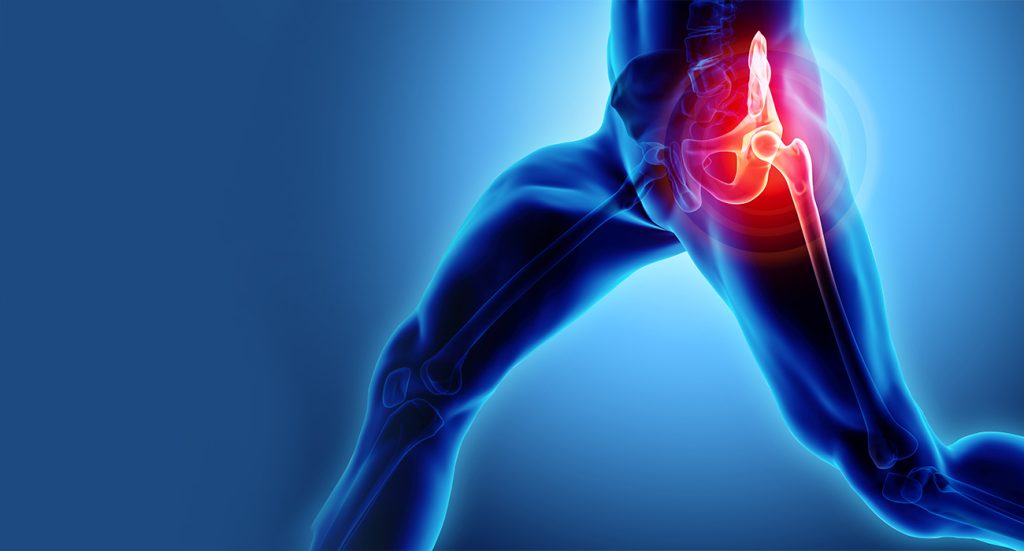

- تعویض مفصل لگن می تواند درد و سفتی مفصل لگن را برای افراد مبتلا به آرتریت، نکروز آواسکولار یا سایر اشکال آسیب مفصل لگن برطرف کند.

تعویض مفصل لگن که به آن آرتروپلاستی لگن نیز گفته می شود، یک روش جراحی برای رفع درد لگن است. در این جراحی قسمت هایی از مفصل لگن با ایمپلنت مصنوعی جایگزین می شود. مفصل لگن از یک توپ (در بالای استخوان لگن ، که به عنوان استخوان لگن نیز شناخته می شود) و یک حفره (در لگن که به عنوان استخوان لگن نیز شناخته می شود) تشکیل شده است. جراحی تعویض مفصل لگن شامل تعویض یک یا هر دو قسمت است. هدف از این روش این است که به شما امکان می دهد فعالیت های روزانه و ورزش را با درد کمتر از سر بگیرید.

در صورت وجود درد، التهاب و آسیب قابل توجه به مفصل لگن به دلیل شرایطی مانند:

- استئوآرتریت (شایع ترین)

- روماتیسم مفصلی

- استئونکروز ( نکروز آواسکولار )

- آسیب هایی مانند شکستگی لگن

- تومور در مفصل لگن

هنگامی که کیفیت زندگی شما به دلیل درد لگن کاهش می یابد، ممکن است زمان تعویض مفصل لگن فرا رسیده باشد. علائم کاهش کیفیت زندگی عبارتند از: